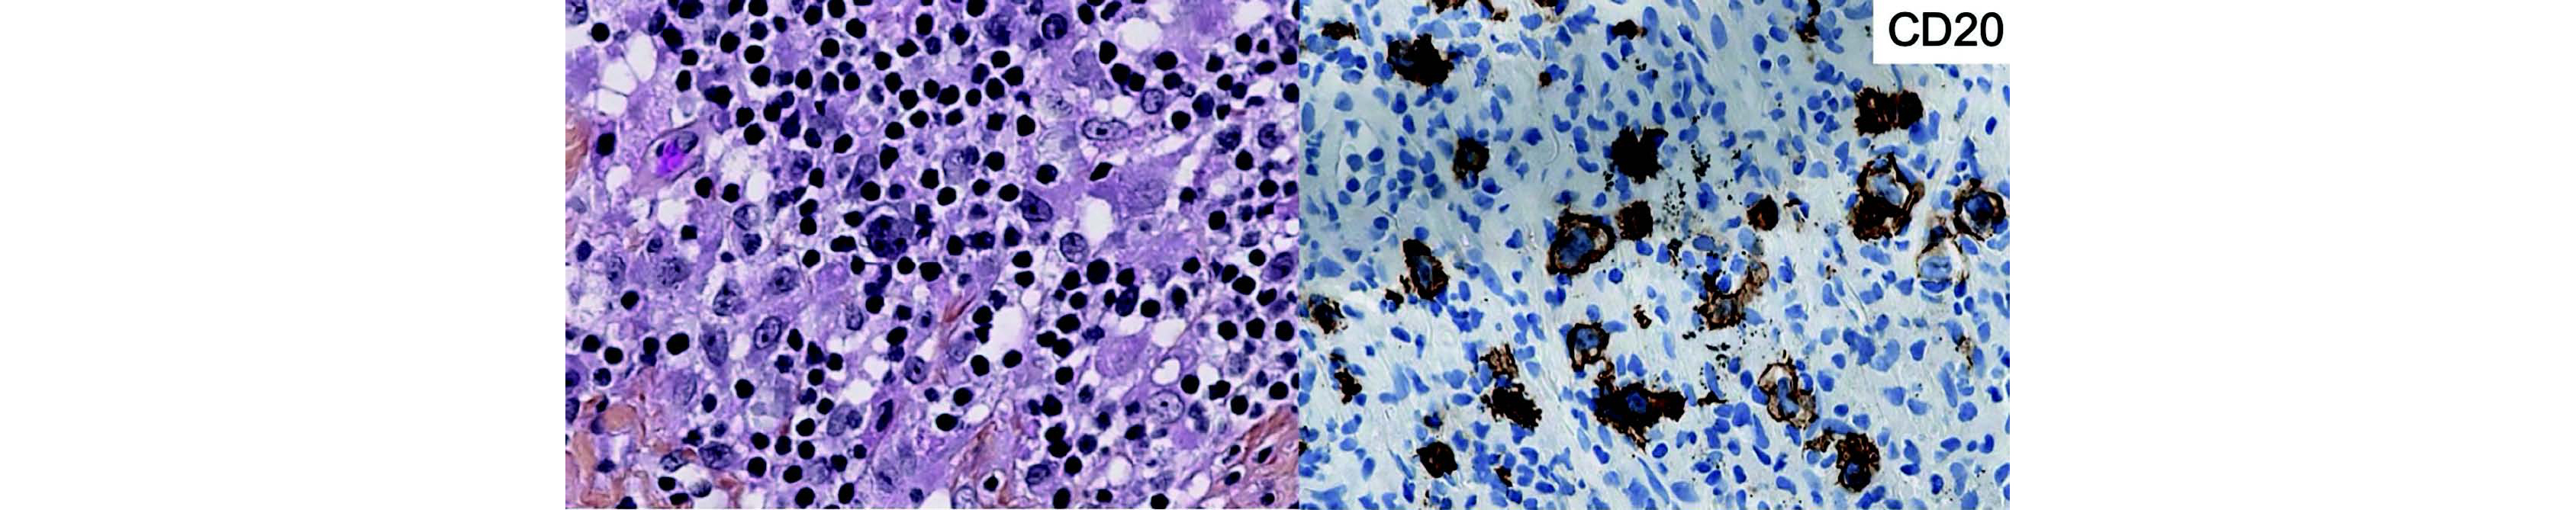

Pour vous récompenser de votre attente, le pathologiste vous envoie une photo, afin de vous tester.

Si vous ne parvenez pas à reconnaître, n'hésitez pas à aller rencontrer vos collègues du laboratoire afin de leur demander !

Figure 11 Photo mystère - À gauche, HPS environ x40 ; À droite, CD20